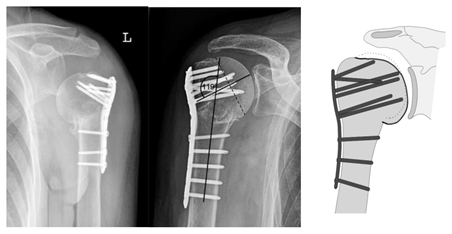

| Complication Type | Exemplary Images by X-rays or Pattern Images | Definition |

|---|---|---|

| 2a | ![]() | Complication Type 2a is defined by varus displacement (<20°) of the humeral head associated with screw cutout through the humeral head cortex. The head sintering is considered relatively stable and non-progressive. |

| 2c | ![]() | Type 2c is defined by a severe varus displacement (>20°) of the humeral head, which is associated with a screw cutout at the humeral head in parallel to Type 2a. In contrast to Type 2a, this varus displacement is characterized by an unstable osteosynthesis situation and progression. |